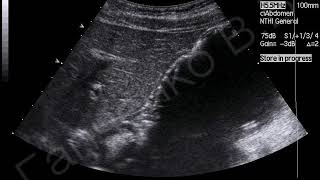

Рак кишечника встречается одинаково часто как у мужчин, так и у женщин — его особенностью являются скудные клинические симптомы на ранних стадиях заболевания. Именно по этой причине тяжелый диагноз определяют только на стадии, когда возможности медицины очень ограничены. Рассмотрим первые признаки рака кишечника, проявления по стадиям и прогностические данные. Рак кишечника — это группа злокачественных новообразований, которые появляются в различных отделах толстого и тонкого кишечника и вызывают тяжелые нарушения работы органов пищеварительного тракта и других систем. В зависимости от расположения опухоли выделяют:. Все злокачественные образования этой области делятся на ряд стадий, в зависимости от распространенности процесса и наличия метастазов. В международной системе рак кишечника классифицируют по системе TNM, где T — размеры первичной опухоли, N — регионарные метастазы, а M — отдалённые метастазы.